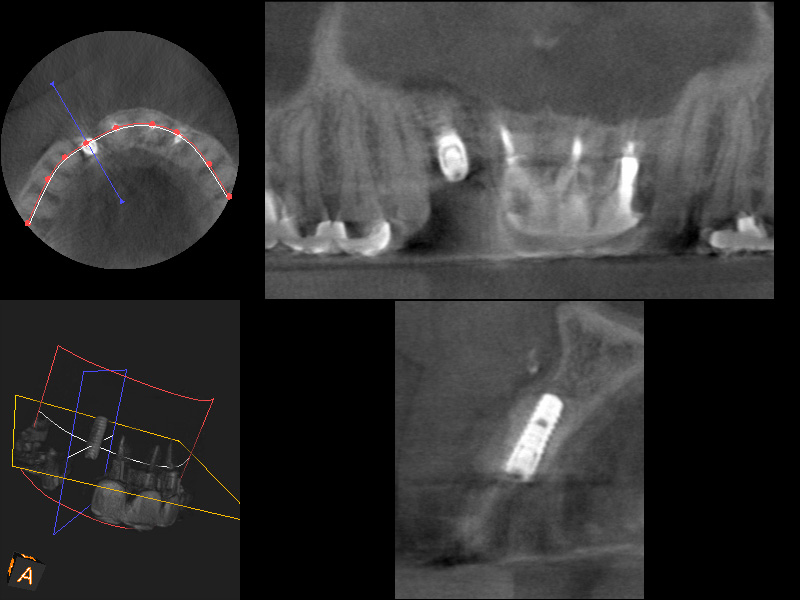

複数の歯に及び歯が失われているためCT画像上で診断と設計を行い、理想的な位置に歯を作ることができるように、サージカルガイドと言われるインプラント手術補助用マウスピースを用いてインプラント手術を行った。

手術の精度を更に上げるサージカルガイド

術前CT

術後CT